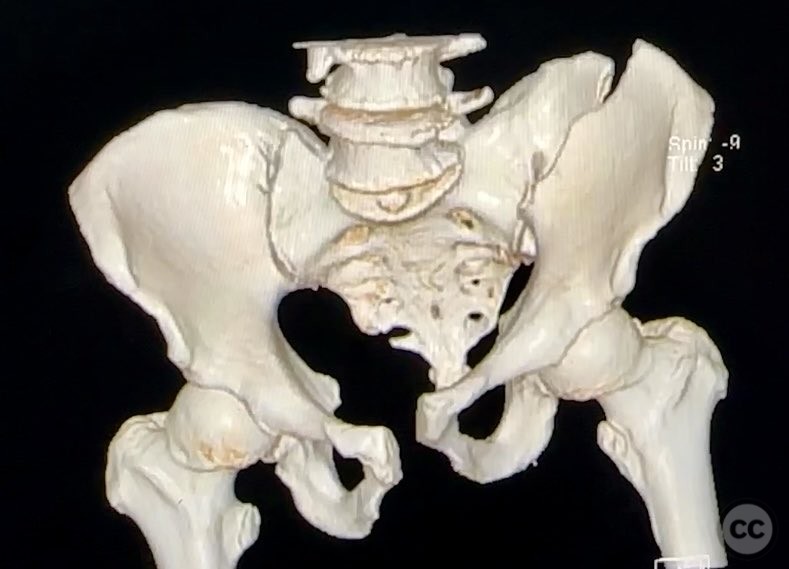

Pelvic Ring - AO/OTA 61x

Pelvis - AO/OTA 6x